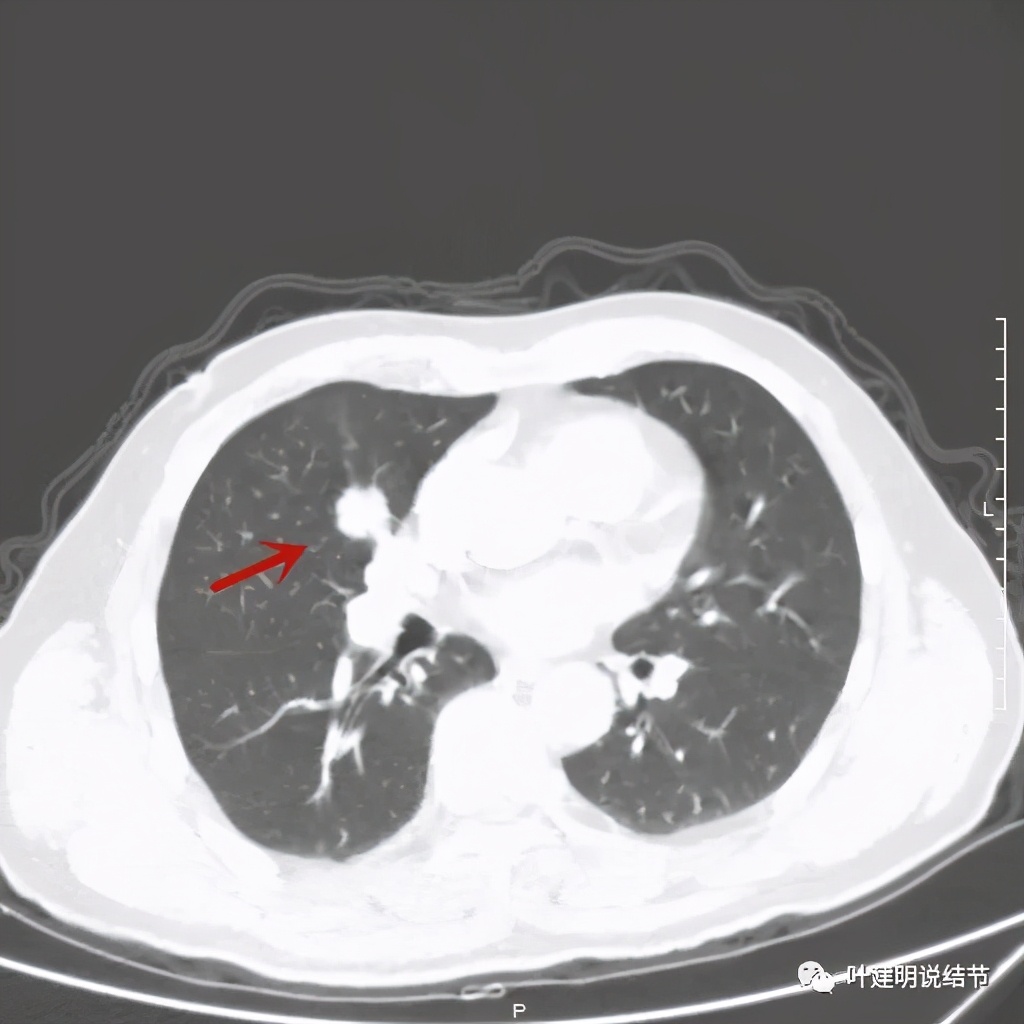

那么当时的胸部影像又是如何的呢?

以上几图示病灶膨胀感明显,无卫星灶,周围无渗出性改变

上图粉色箭头示细毛刺征,蓝色似支气管截断,红色示病灶膨胀性明显